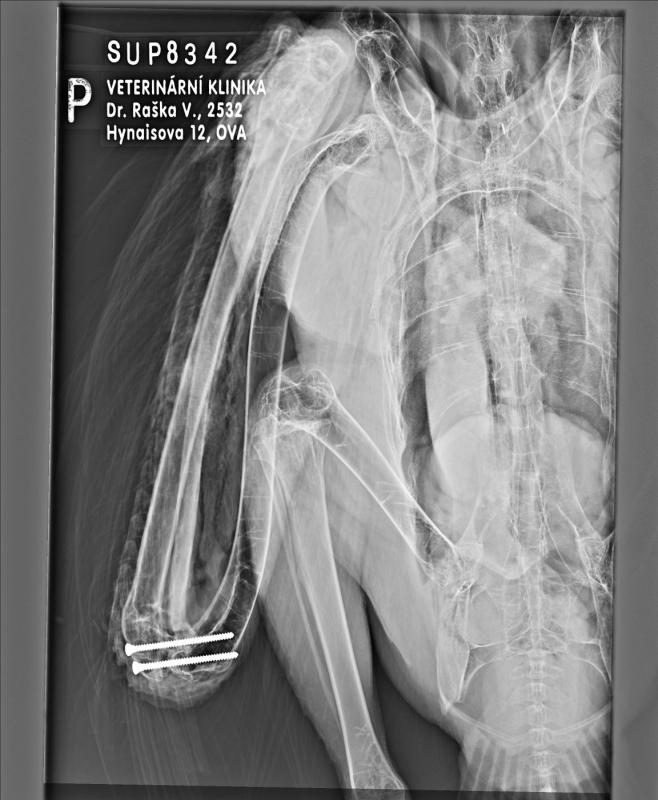

Chovatelům bylo jasné, že supice bude trvale handicapovaná, přesto chtěli zraněné křídlo zachránit. Věděli jsme, že vzhledem ke komplikované několik dní staré zlomenině létat už nebude, ale s křídlem i když nefunkčním má pták větší stabilitu a má větší šanci se úspěšně pářit. Několikatýdenní bandáž křídla sice zajistila srůst kostí, ale křídlo zůstalo svěšené a vadilo jí v pohybu. Proto jsme na začátku letošního roku v rámci nezištné spolupráce s MVDr. Raškou a jeho kolektivem přistoupili k operaci, jejímž cílem bylo omezit pohyb v loketním kloubu a tím křídlo trvale pozvednout k tělu. Operace trvala víc než dvě hodiny a skončila úspěšně. Samice byla velmi dobrý pacient. Po dokonalém zhojení ran a krátké rekonvalescenci byla na doporučení evropského koordinátora chovu supů bělohlavých v dubnu 2024 převezena do Bioparku ve Francii. Zde je umístěna ve velké otevřené voliéře, kterou obývá s několika podobně handicapovanými supy.